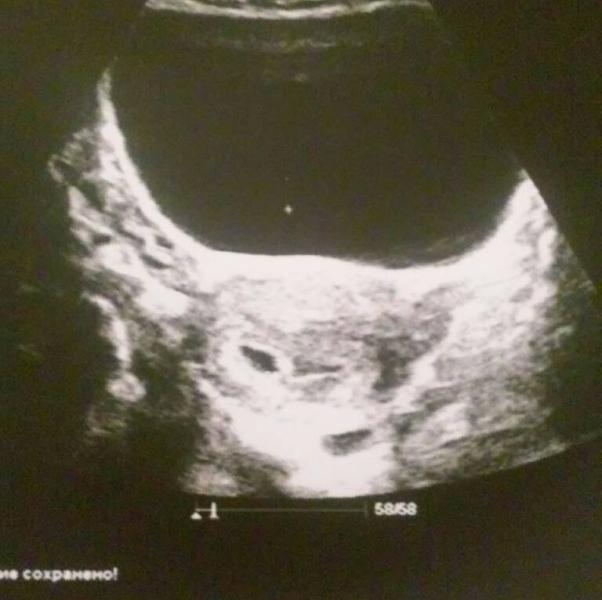

Ура, детка прикрепился куда нужно) Тонуса нет, матка из ретрофлексио повернулась в нормальное положение. Жёлтое тело вопреки логике и очередности в левом яичнике, там где у меня и побаливало несколько дней назад. По УЗИ срок 5 недель 2 дня, как раз у меня овуляция обычно не на 14й, а на 19й день цикла. Всё сошлось)

Вот казалось бы у меня в руках его фотография, а мне всё равно не верится, что у нас будет ребенок 👶